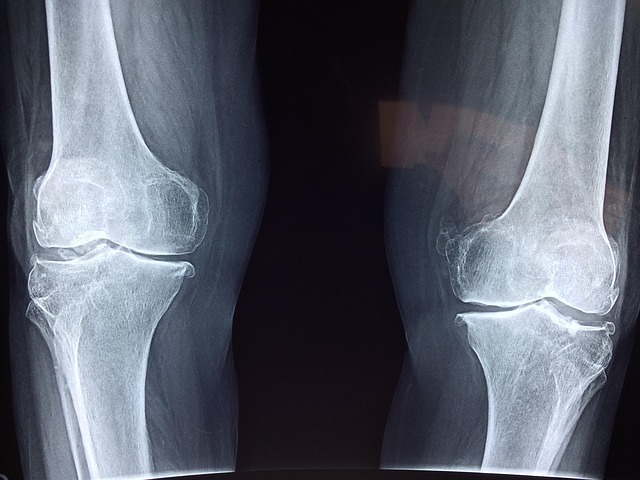

Osteoarthritis is usually framed as the price of just getting older. Many people imagine a knee that slowly wears down, then never recovers. That picture is familiar, yet it is too simple. Osteoarthritis affects the whole joint. It can hurt cartilage, bone, lining tissue, movement, sleep, and daily confidence. The World Health Organization says the knee is most commonly affected. It also says hundreds of millions live with osteoarthritis worldwide. NIAMS also explains that the disease is not just surface wear. It involves changes across joint tissues over time.

For many people, osteoarthritis becomes a slow narrowing of normal life. Stairs take more planning. Walking farther takes more grit. Even sitting too long can set off stiffness. The National Institute on Aging is blunt. “There is no cure for osteoarthritis.” That explains why new studies draw attention. Current treatment usually aims to reduce pain, improve function, and delay further damage. Exercise, weight control, supportive devices, pain medicine, injections, and surgery all have a place. Yet none of them fully solves the underlying disease for most people. The World Health Organization also says osteoarthritis is “not an inevitable consequence of ageing.” So the condition is common. Yet it is not just an unavoidable decline. Something goes wrong inside the joint, and researchers want to understand exactly what that is.

When people hear about semaglutide helping osteoarthritis, they are really hearing a bigger question. Can medicine do more than help people cope? Can it help damaged joint tissue recover enough to change the course ahead? The scale of the problem helps explain the excitement. The World Health Organization estimated that 528 million people lived with osteoarthritis in 2019. A 2023 Global Burden of Disease analysis in The Lancet Rheumatology estimated 595 million cases in 2020. That equals about 7.6% of the global population. That analysis projected even more cases by 2050. Knee osteoarthritis carries a large share of that burden. It limits mobility, and mobility shapes almost every other part of health. Less walking often means less strength, more weight gain, worse blood sugar control, poorer sleep, and more isolation.

Exercise and physical therapy can improve pain and function, and weight loss can lower stress on the knee, but these approaches demand time, consistency, and enough pain control to stay active. NIAMS says treatment usually starts with exercise, while NICE recommends therapeutic exercise and weight management as core parts of care. Yet many people still reach a point where tablets, topical gels, braces, or injections bring only partial relief. Surgery can help when damage becomes severe, but it is usually a later step, not a simple fix. That leaves a large middle ground of people who are not well, yet are not ready for joint replacement either. In that uncomfortable space, even a small sign that a medicine might protect cartilage, not just dull pain, feels like a meaningful shift in the story of osteoarthritis for millions living with it.